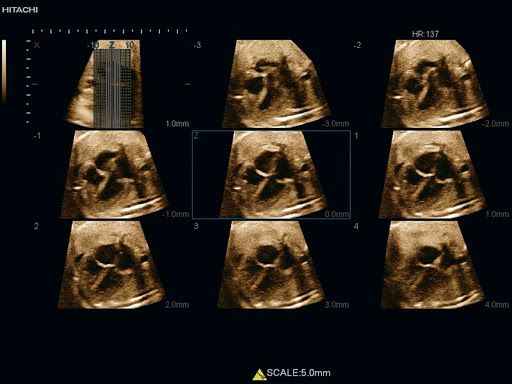

EUP-CV724 – Объёмный конвексный датчик, предназначенный для трёхмерного трансабдоминального сканирования. К преимуществам датчика относятся широкий частотный диапазон, большой пространственный охват области интереса и эргономичный корпус. Благодаря этим особенностям, возможно полное исследование зоны интереса и окружающих структур по всей глубине.